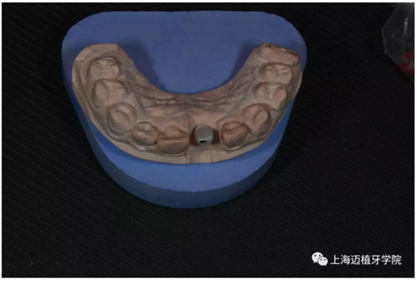

取工作模型

非工作模型

氧化鋯個性基臺